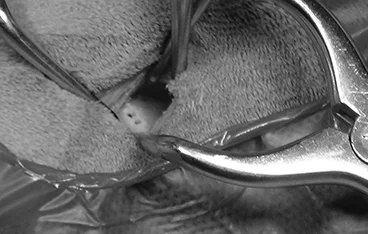

• TECA+LBO 수술 전

TECA+LBO 수술 후